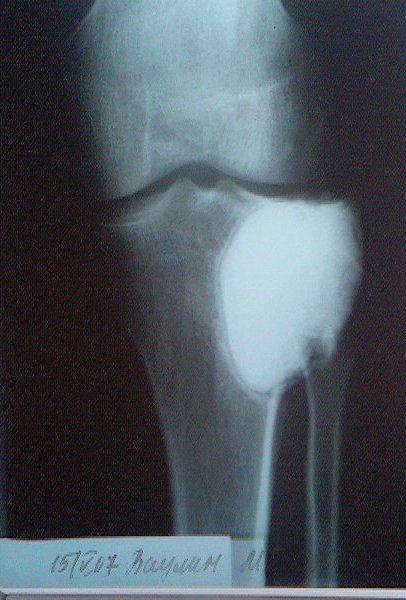

[Ortho] пластика мыщелка б\б кости

около года назад больному 25 лет по поводу литической опухоли мыщелка

б\б кости ( ОБК?)с выраженным болевым синдромом была произведена

расширенная открытая биопсия, экскохлеация опухоли. В связи с

неясностью диагноза до операции и отсутствия аллокости в тот момент

интраоперационно было выполнено экспресс протезирование дефекта

мыщелка акриловым цементом. Верхней стенкой дефекта была визуально

неповрежденная суставная поверхность. Хрящевая пластина провисала -

была выведена на уровень и "подперта" цементным спейсером. Больной

осмотрен через год - ходит не хромая, сустав абсолютно спокойный,

рентгенологически процедива опухоли нет. Хотелось бы услышать

предложения по пластике дефекта - сроки, вид материала. Честно говоря

боюсь трогать хрящ повторно.